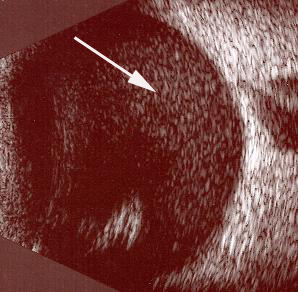

Resim 1: Normal göz ultrasonu görüntüsü. Beyaz ok göz sıvısını (vitreus) , siyah ok retina tabakasını göstermektedir.